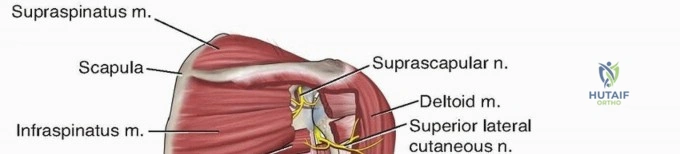

The radial nerve is the most critical anatomical structure at risk during both the initial injury and subsequent surgical approaches to the humerus. The nerve, accompanied by the profunda brachii artery, exits the axilla and passes through the triangular interval. This interval is bordered superiorly by the teres major, medially by the long head of the triceps, and laterally by the humeral shaft.

From the triangular interval, the radial nerve transverses from medial to lateral along the posterior aspect of the humeral shaft within the spiral groove. It pierces the lateral intermuscular septum approximately 10 to 12 centimeters proximal to the lateral epicondyle to enter the anterior compartment of the arm. Distally, the nerve travels in the anatomic interval between the brachialis muscle medially and the brachioradialis muscle laterally. This specific interval is the foundation of the distal anterolateral approach to the humerus.

The musculocutaneous nerve also requires consideration during the anterior approach. It pierces the coracobrachialis proximally, lies on the undersurface of the biceps brachii muscle, and rests superficially on the brachialis muscle. It provides motor innervation to the medial portion of the brachialis before terminating distally as the lateral antebrachial cutaneous nerve. The dual innervation of the brachialis—medial half by the musculocutaneous nerve and lateral half by the radial nerve—permits longitudinal splitting of the brachialis muscle during the anterolateral approach without causing complete denervation.

For midshaft fractures, the brachialis muscle is split longitudinally down its midline. Because the medial half is innervated by the musculocutaneous nerve and the lateral half by the radial nerve, this longitudinal split is an internervous plane that preserves the function of both segments. The split is carried down to the periosteum, and the muscle halves are elevated off the anterior humerus. The lateral half of the brachialis acts as a protective muscular cushion between the retractor (and subsequently the plate) and the radial nerve.

For distal third fractures, the exposure must transition to the interval between the brachialis and the brachioradialis. The radial nerve emerges from the posterior compartment by piercing the lateral intermuscular septum and travels distally in the cleft between the brachialis (medially) and the brachioradialis (laterally).

To safely exploit this interval, the fascia between the brachialis and brachioradialis is carefully incised. The radial nerve must be actively identified and protected. It is often easiest to identify the nerve distally where the interval is wider and trace it proximally to where it pierces the septum. Once identified, the nerve is gently mobilized and protected with vessel loops. Retraction of the nerve must be minimal and meticulous to prevent iatrogenic neuropraxia.